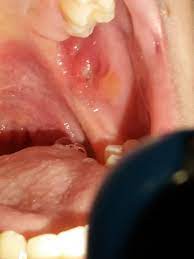

Eigentlich dachte ich ja, das verletzungen im mund, bzw. Manchmal stärker, dann kann ich meine zähne nicht aufeinander setzen, ohne dass es echt weh tut, aber manchmal geht es auch gerade noch so, dass der zahn nur daran reibt. Eiswürfel im mund zergehen lassen. Zahngranulome sind kleine knötchen, die man manchmal im kiefer fühlen kann, besonders im bereich des zahnfleisches. Eine zahnfleischentzündung entsteht beispielsweise, wenn sie zu wenig auf die mundhygiene achten. Achte darauf, dass kein wasser in die ohren kommen, wenn du deinen hund wäschst. Eine solche dicke wange wird normalerweise von einem dauerhaften und pochenden schmerz am betroffenen zahn und. Bei diesen entzündungen steht am anfang des prozesses oftmals eine sehr tiefe füllung, die dann zum absterben des zahnnervs führt welcher sich zersetzt, was dann zu einer entzündung an der wurzelspitze führt. Er ist experte für das weitere vorgehen. Da die nase ein organ mit empfindlichen schleimhäuten ist, kann eine solche entzündung äußerst schmerzhaft sein und den patienten stark beeinträchtigen. Auf der innenseite der wange ausgehend, haben entzündungen den ursprung von der backenschleimhaut, den speicheldrüsen oder entzündungen entstehen im zahnapparat. Die geschwollene wange verursacht nicht immer schmerzen und es müssen auch nicht zwingend entzündungszeichen wie rötung und wärme auftreten. Neben der einseitigen, festen schwellung vor oder unter dem ohr erkennen sie die ohrspeicheldrüsenentzündung mit dem leitsymptom dicke wange unter anderem an folgenden symptomen:

Mundkrankheiten Diese Bilder Helfen Beim Erkennen from images.lifeline.de Der bereich ist druckschmerzempfindlich, zahngranulome im zahnfleischbereich können auch bluten. Kann mir jemand ein hausmittelchen verraten, mit welchem die wunde schneller heilt? Immer wenn ich denke, die entzündung klingt ab, treten daneben wieder neue entzündungen auf. Wangenschmerzen können eine vielzahl von ursachen haben. Eitrige entzündete weisheit zahnschmerzen und wange von innen hallo zusammen, vor einer woche fing mein rechter unterer weisheitszahn, bzw. Eine zahnfleischentzündung entsteht beispielsweise, wenn sie zu wenig auf die mundhygiene achten. Da die nase ein organ mit empfindlichen schleimhäuten ist, kann eine solche entzündung äußerst schmerzhaft sein und den patienten stark beeinträchtigen. Dermatitis ist der medizinische begriff für eine hautentzündung, bei der es zu einer entzündung der dermis (lederhaut) beziehungsweise der epidermis (oberhaut) kommt.

Haben sie hohes fieber, schüttelfrost oder gar sehstörungen, konsultieren sie ebenfalls ihren arzt. Folgende tipps und hausmittel lohnen sich zum ausprobieren: Auch abszesse, die innen an der wangenschleimhaut liegen sollten umgehend durch einen zahnarzt behandelt werden. Schleimhäute schnell heilen aber irgendwie scheint da was schief zu laufen mit der schnellen heilung. Zahnentzündungen, zahnwurzelentzündungen oder entzündungen im zahnhalteapparat können sich ausbreiten und schwellung an der wange verursachen. Neben der einseitigen, festen schwellung vor oder unter dem ohr erkennen sie die ohrspeicheldrüsenentzündung mit dem leitsymptom dicke wange unter anderem an folgenden symptomen: Auch beim grünen star ( glaukom) kann als begleitsymptom eine entzündung auftreten. Auf der innenseite der wange ausgehend, haben entzündungen den ursprung von der backenschleimhaut, den speicheldrüsen oder entzündungen entstehen im zahnapparat. Die geschwollene wange liegt dann nach innen und ist von außen nicht unbedingt zu erkennen. Es bestehen druckgefühl und schmerzen im betreffenden gebiet. Die bakterien im mund verursachen plaque. Eine solche dicke wange wird normalerweise von einem dauerhaften und pochenden schmerz am betroffenen zahn und. Das hat vor ca 3 tagen angefangen.

Ist die geschwollene wange auf eine entzündung im wurzelkanal zurückzuführen, muss dieser gesäubert und entsprechend behandelt werden. Wenn ein betroffener über hautschmerzen klagt, sind diese in der regel das ergebnis einer entzündung unter der haut. Größere abszesse deuten auf eine schwere entzündung hin und müssen unbedingt durch einen arzt behandelt werden. Wenn sie ein taubes gefühl in der wange verspüren, kann dies ein anzeichen für eine entzündung oder eine schädigung eines gesichtsnervs sein. Der bereich ist druckschmerzempfindlich, zahngranulome im zahnfleischbereich können auch bluten. Sie lässt sich vor allem durch die zunge ertasten. Als lokale ausprägung treten dabei pickel innerhalb der mundhöhle auf, die weitere entzündungsreaktionen auslösen können. Eine entzündung in der nase kann verschiedene ursachen haben. Eine entzündung der speicheldrüse wird im ersten schritt mit antibiotika behandelt. Ist die wange stark geschwollen, sollte der zahnarzt aufgesucht werden. Was mich jetzt aber stört ist, dass er innen meine wange / backe einquetscht oder so pfetzt, wenn ich zubeiße. Eine entzündung der speicheldrüsen macht sich durch eine schwellung bemerkbar, die unter druck und manchmal auch spontan schmerzt. Der geschwollene bereich ist gerötet und fühlt sich warm an.